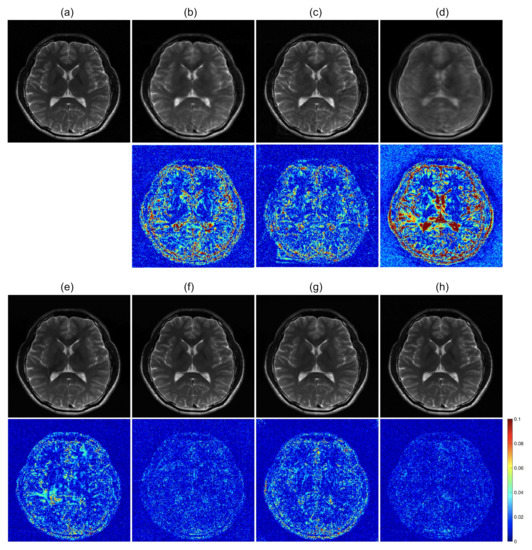

To further optimize the proposed network for image reconstruction, two different losses were additionally calculated along with the baseline loss function of the Euclidean distance: adversarial loss and perceptual loss. The effects of the loss functions were analyzed for the undersampled k-space data with R = 4. The ETER-net with different loss functions was also compared with two different image-domain to image-domain reconstruction methods, DFU [27] and DAGAN [19], and a k-domain to k-domain reconstruction method, k-space deep learning for accelerated MRI [16]. Figure 7 shows the result images and errors, and Figure 8 shows the quantitative analysis of the reconstructed images. Figure 7b,c show a substantial amount of image artifacts and aliasing patterns, owing to the regular subsampling of the input k-space data. In contrast, the proposed methods show quality results, and the aliasing artifacts are eliminated in these images (columns (e–h)). By comparing the images reconstructed with various loss functions, it can be concluded that the loss functions, including the Euclidean distance, adversarial loss, and perceptual loss, provided the best performance in terms of image quality.

Figure 7.

Comparison of previous methods with the proposed method. first and third row: Magnitude images. second and fourth row: Corresponding error maps in the 1/10 range. (a): Ground truth magnitude images (label images). The images are reconstructed by (b): DFU, (c): DAGAN, (d): k-space deep learning, (e): baseline loss, (f): baseline loss + perceptual loss, (g): baseline loss + adversarial loss, and (h): baseline loss + adversarial loss + perceptual loss.

Quantitative analysis of DFU, DAGAN, and the proposed methods with/without additional losses. nMSE and SSIM were measured from 64 slices of four subjects. U-net, DAGAN, kspDL: comparison methods, ETER: with baseline loss function of pixel-wise Euclidean distance, GAN: with additional adversarial loss function, VGG: with additional perceptual loss via pre-trained VGG network, GAN + VGG: with additional adversarial and perceptual loss functions.